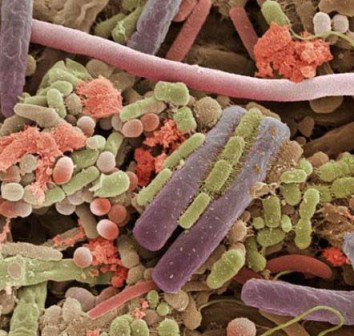

باکتری هایی که روی زبان انسان قرار گرفته اند.

پلاک دندان